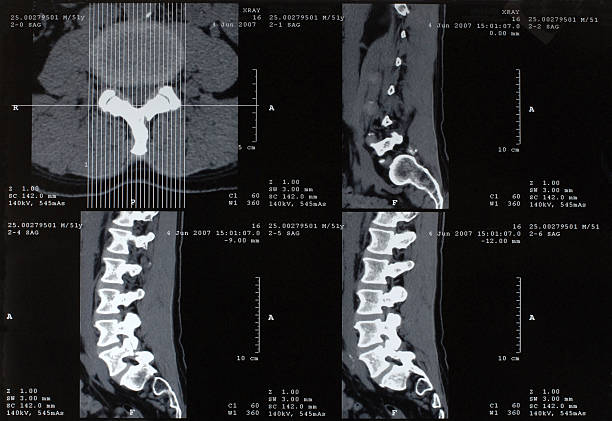

허리디스크는 디스크가 변형되고 압박이 발생하는 위치와 정도에 따라 다양한 증상이 나타날 수 있습니다.

그리고 허리디스크의 치료법은 환자의 증상과 디스크의 상태에 따라 다양하게 적용됩니다.

허리디스크의 가장 흔한 증상 중 하나는 허리 부위에서 발생하는 통증입니다. 이 통증은 디스크의 압박 정도와 위치에 따라 다르며, 통증의 정도도 다를 수 있습니다.

디스크가 허리 신경에 압박을 가할 경우, 다리로 통증이나 저림 현상이 느껴질 수 있습니다. 이러한 증상은 흔히 "발바닥 저림"과 같은 형태로 나타날 수 있습니다.

허리디스크로 인해 허리 주변 근육의 기능이 저하될 수 있습니다. 이로 인해 근육 약화와 함께 움직임에 제약을 받을 수 있습니다.

허리디스크의 증상은 시간이 지남에 따라 호전될 수도 있고 악화될 수도 있습니다. 증상이 어떻게 진행되는지는 디스크의 상태와 환자의 개인적인 상황에 따라 다를 수 있습니다.